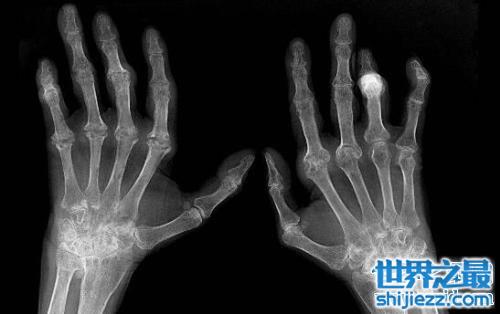

5.类风湿

患有类风湿这种疾病的人,虽然不会导致死亡,但是这种绝症确实一个非常折磨人的疾病,只要周围的环境发生了一点点变化,都会引起关节疼痛,严重的还有肯会因此而终生残疾,也是世界五大绝症中的一大绝症了。